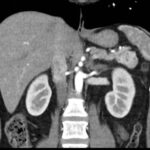

Paciente femenina de 48 años de edad que ingresa a Hospital Sanatorio Franchin por síntomas de cefalea y mareos, cuadro que se hace progresivo, presentando síncopes y posteriormente alteración del estado de conciencia. Los exámenes clínicos revelan una glucosa de 40 mg/dl, concomitante con insulina alta y péptido C elevado. Ingresa de forma programada para realización de duodeno pancreatectomía el 29 de mayo de 2021. Imágenes diagnósticas muestran estudio trifásico de tomografía de abdomen, lesión nodular en la cabeza del páncreas con ávido realce en fase arterial que en resonancia magnética se observa hiperintensa en T2, presenta restricción con la difusión y caída de la señal en el ADC. Además presenta realce tras la administración de contraste con gadolinio.